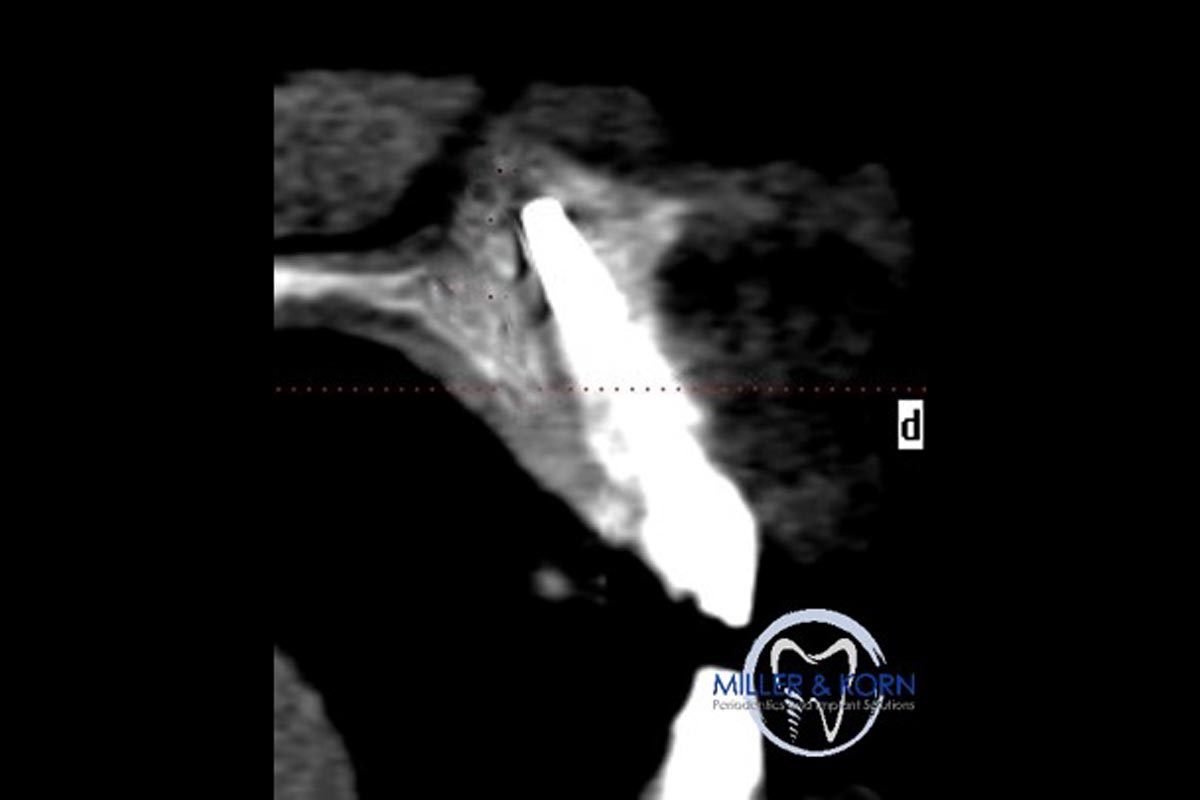

38/39 - Preoperative CT scanImmediate implant placement and correction of horizontal and vertical bone loss using an allograft bone ring, cerabone® and Jason® membrane - Drs. Miller and Korn

DVT image demonstrating horizontal and vertical amount of bone available

The patient presented with pathologic mobility of upper left central incisor. Radiographic examination revealed significant circumferential attachment loss with an unfavorable crown to root ratio.